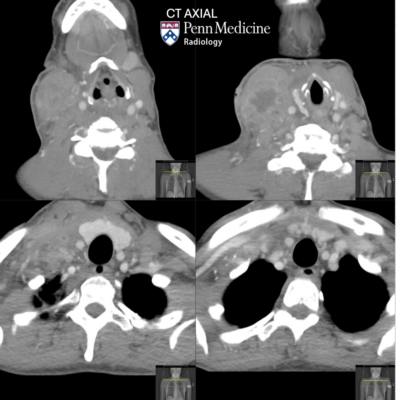

CT: There is a large intramuscular abscess within the inferior right sternocleidomastoid muscle with overlying cellulitis within the right anterolateral neck and reactive cervical lymphadenopathy. The airway is patent. There is associated thrombophlebitis of the right internal jugular vein, concerning for Lemierre syndrome.

Diagnosis: Lemierre syndrome